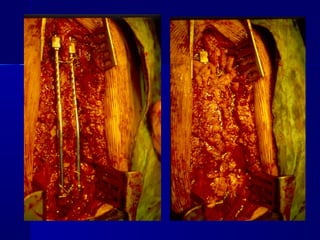

AAnntteerriioorr PPrroocceedduurree

Anterior – Posterior decompression aanndd ssttaabbiilliizzaattiioonn

oonnee –– ttwwoo sseessssiioonnss

IIMMPPLLAANNTTSS

IImmppllaannttss ffoorr

AAnntteerriioorr

CCoorrrreeccttiioonn

aanndd

SSttaabbiilliizzaattiioonn

ffoorr

PPoosstteerriioorr

AAnntteerriioorr --

CCoorrrreeccttiioonn aanndd